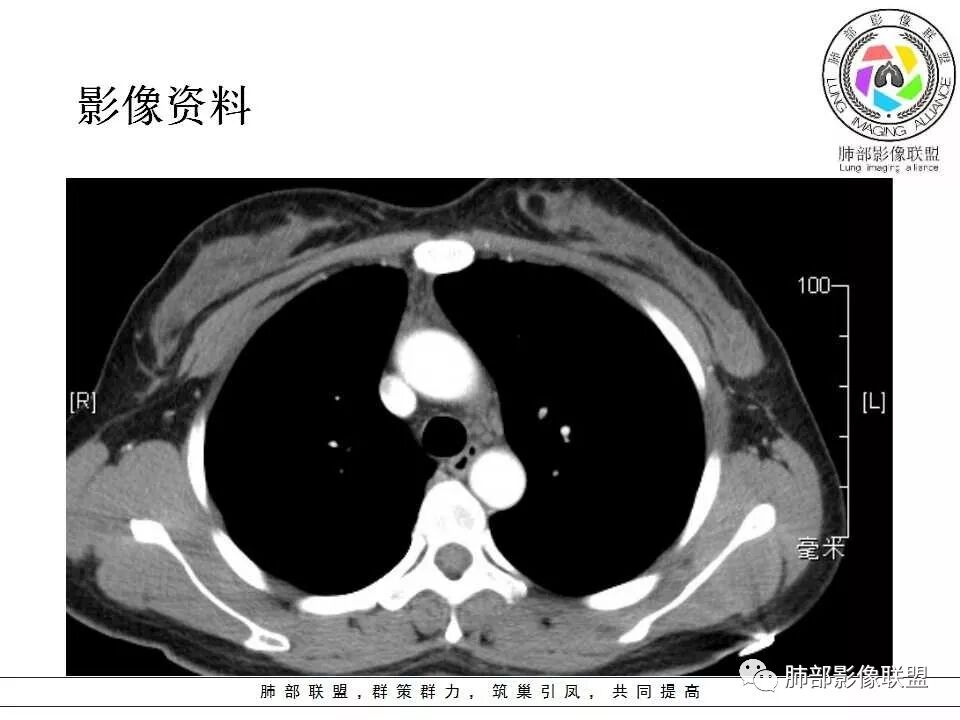

左肺门肿块,边缘光滑清晰,血管贴边,明显均匀强化,考虑PSP,鉴别类癌。

学习一下南大的诊断思路,左肺门区病灶,应该没跨叶,感觉都在上叶,强化密度均匀,边缘清晰,与支气管关系不大,常规考虑良性病变,PSP可能性大,鉴别CD,血管源性。但是一年增大怎么解释,不知道增大多少。

左肺病灶与支气管关系密切,类癌粘膜下生长,支气管略变窄,支气管外病变较大,符合冰山征表现,一年内有增长,考虑类癌,鉴别PSP,建议薄层重建。

我怎么又感觉跨叶间裂了,而且有胸膜尾征和可疑的指状突起,强化很明显,考虑SFT可能大,鉴别类癌和CD

患者中年女性,发现左肺上叶占位,随访发现体积增大。胸部CT:左肺上叶尖后段实性占位,位于支气管旁,未见支气管阻塞,病灶边界清楚,边缘光滑,增强可见病灶均匀强化,血管贴边,考虑良性病变,PSP?

患者中年女性,发现左肺上叶占位1年余入院,随访发现体积增大。胸部CT:左肺上叶尖后段近肺门及叶间裂实性类圆形结节,病灶边界清楚光滑,增强可见病灶明显均匀强化,其旁未见支气管堵塞。综合考虑良性病变,孤立性纤维瘤可能,鉴别巨大淋巴结增生症及硬化性肺细胞瘤。

中年女性,发现左肺上叶占位。胸部CT:左肺上叶尖后段孤立卵圆形实性病灶,位于支气管旁,边界清楚,边缘光滑,血管贴边,肺动脉为主征,增强扫描明显均匀强化。考虑:PSP?鉴别CD、类Ca。

左肺上叶类圆形实性病灶,边缘光滑,可见血管贴边征,病灶与左肺上叶支气管关系密切,左肺动脉相对增粗,增强病灶均匀强化,常规考虑PSP,其次神经内分泌肿瘤不排除。

36岁女性,发现左肺占位1年,时有干咳。CT:左肺门(上叶尖后段?)类圆形结节,边界清,靠前边缘似有GG0,近肺门侧与血管密切接触,似有小凸起,增强见明显均匀强化,似有条片状影往肺门侧血管钻。图片有点少,病灶与支气管的关系看不清(目前的图片与支气管不密切)。随诊结节增大,整体考虑典型类癌可能性大,鉴别硬化性肺细胞瘤。